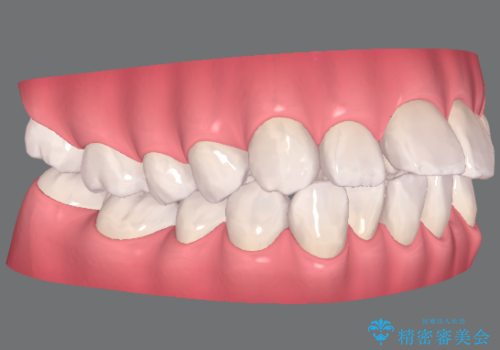

捻れた奥歯 突き出た前歯を治したい

- 出っ歯に見える前歯、捻れてしまった小臼歯の改善を求めて来院されました。

マウスピースでは改善の難しい小臼歯のねじれをまず部分ワイヤー矯正で改善し、その後マウスピース矯正で前歯の突出感を改善します。